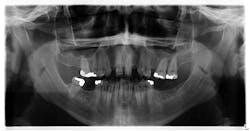

Upon initial assessment, the panoramic radiograph is insignificant (figure 3).